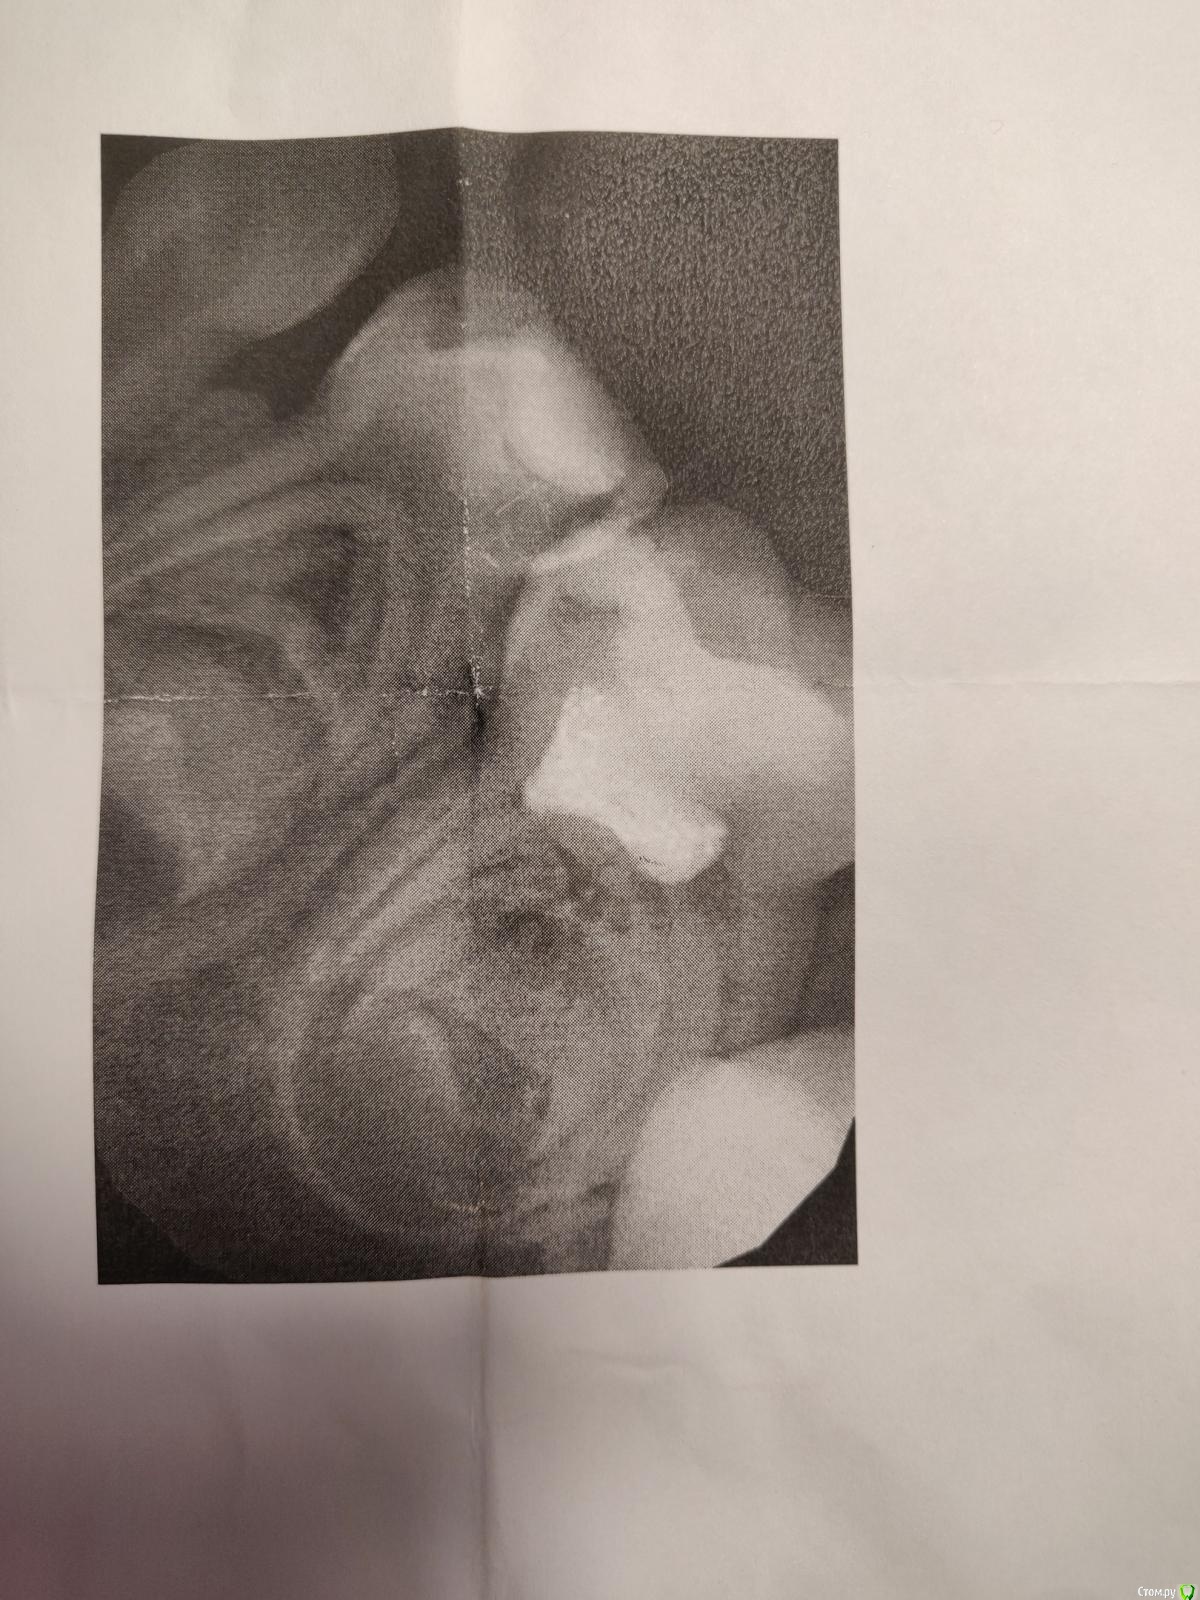

Здравствуйте, ребенку 4 г. 2-3 месяца назад на зуб поставили пломбу в бесплатной поликлинике. На днях у другого врача в платной клинике на осмотре сделали рентген этого зуба и сказали, что нужно срочно переделывать. Подскажите, пожалуйста, это действительно срочно? И если да, то маска с закисью азота - это безопасно для ребенка в качестве анестезии?